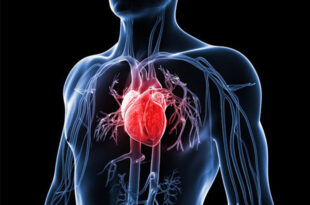

भारत में दिल की बीमारियां सबसे बड़ी मौतों की वजह बनी हुई हैं। खासकर हार्ट अटैक यानी दिल का दौरा, जो कई बार बिना किसी पूर्व चेतावनी के अचानक हो जाता है। लेकिन क्या सच में हार्ट अटैक अचानक होता है? विशेषज्ञों की मानें तो हार्ट अटैक से पहले शरीर कई बार ऐसे संकेत देता है जिन्हें नजरअंदाज करना भारी …